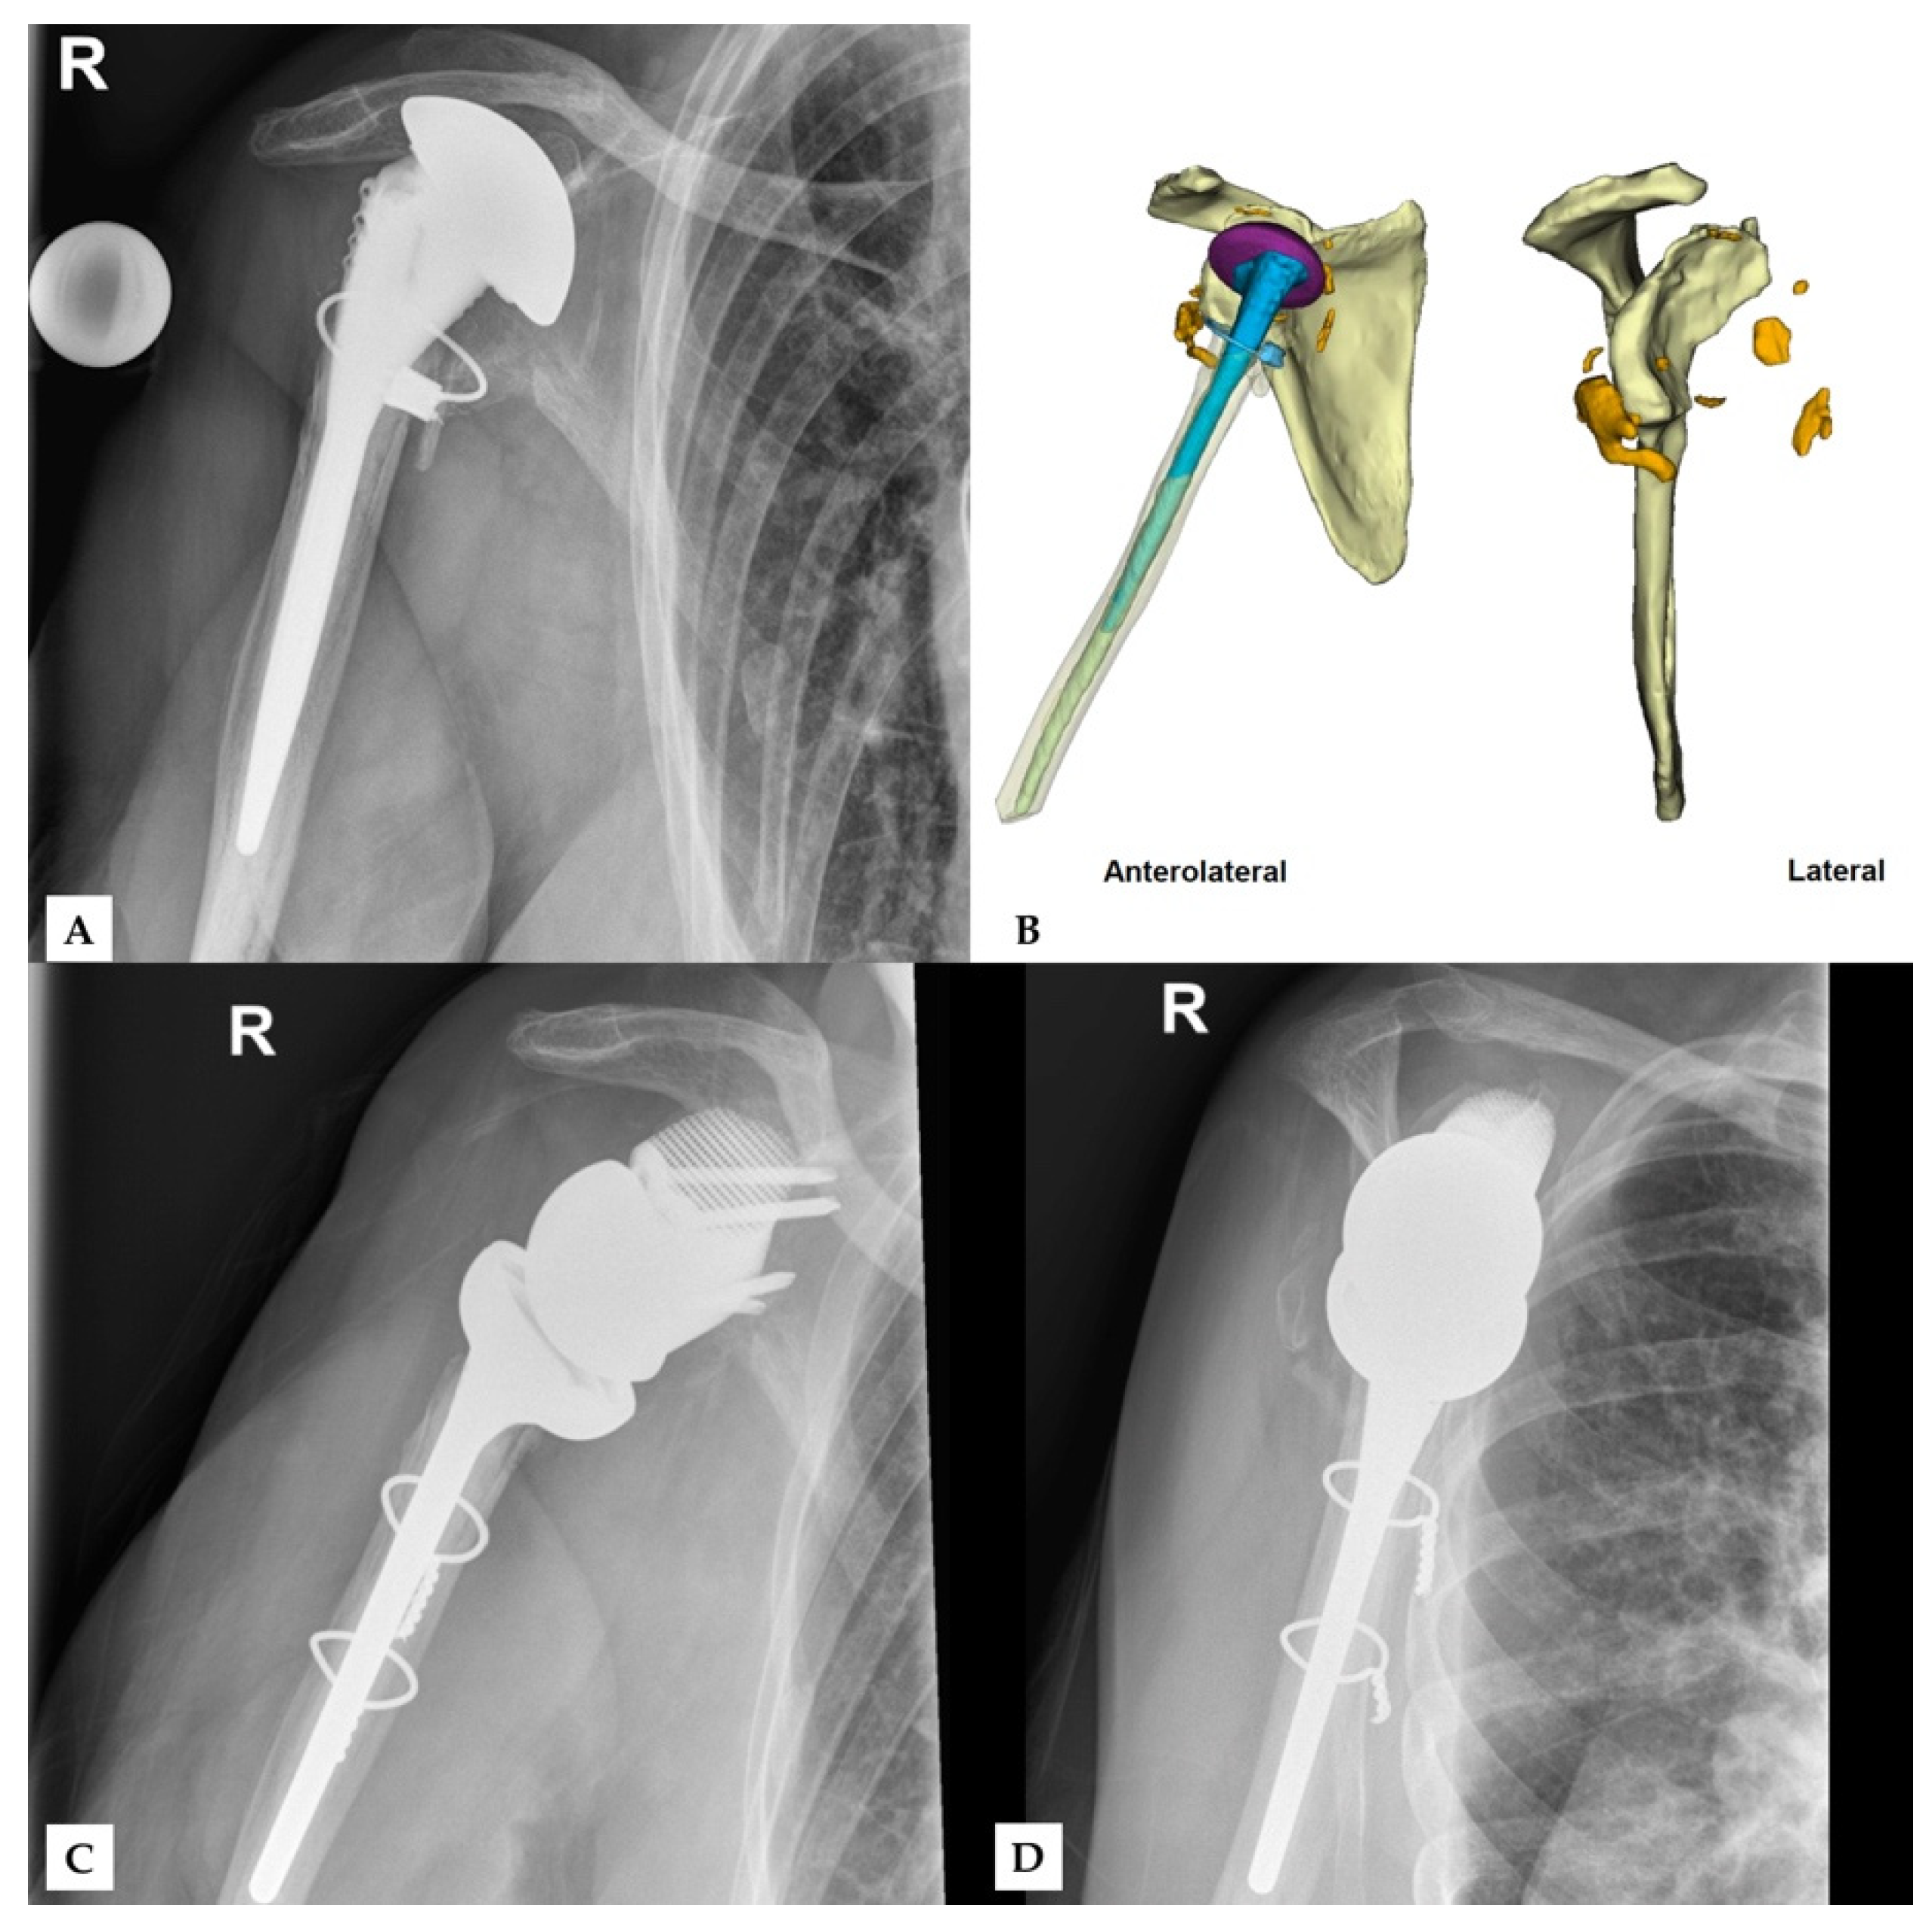

Finally, no complications were observed during surgery or in follow-up. Figure 4 and Figure 5 show two patients who received revision rTSA. The patients are very happy with the outcome. Considering the devastating initial situation, the comparison between preoperative X-rays and postoperative X-rays shows an excellent result.

Figure 5. Third case of a revision rTSA. The preoperative situation is displayed in the images on the top (A,B). The bottom images show the outcome in AP (C) and lateral direction (D). Reprinted with permission from Materialise. ©2021 Materialise NV.